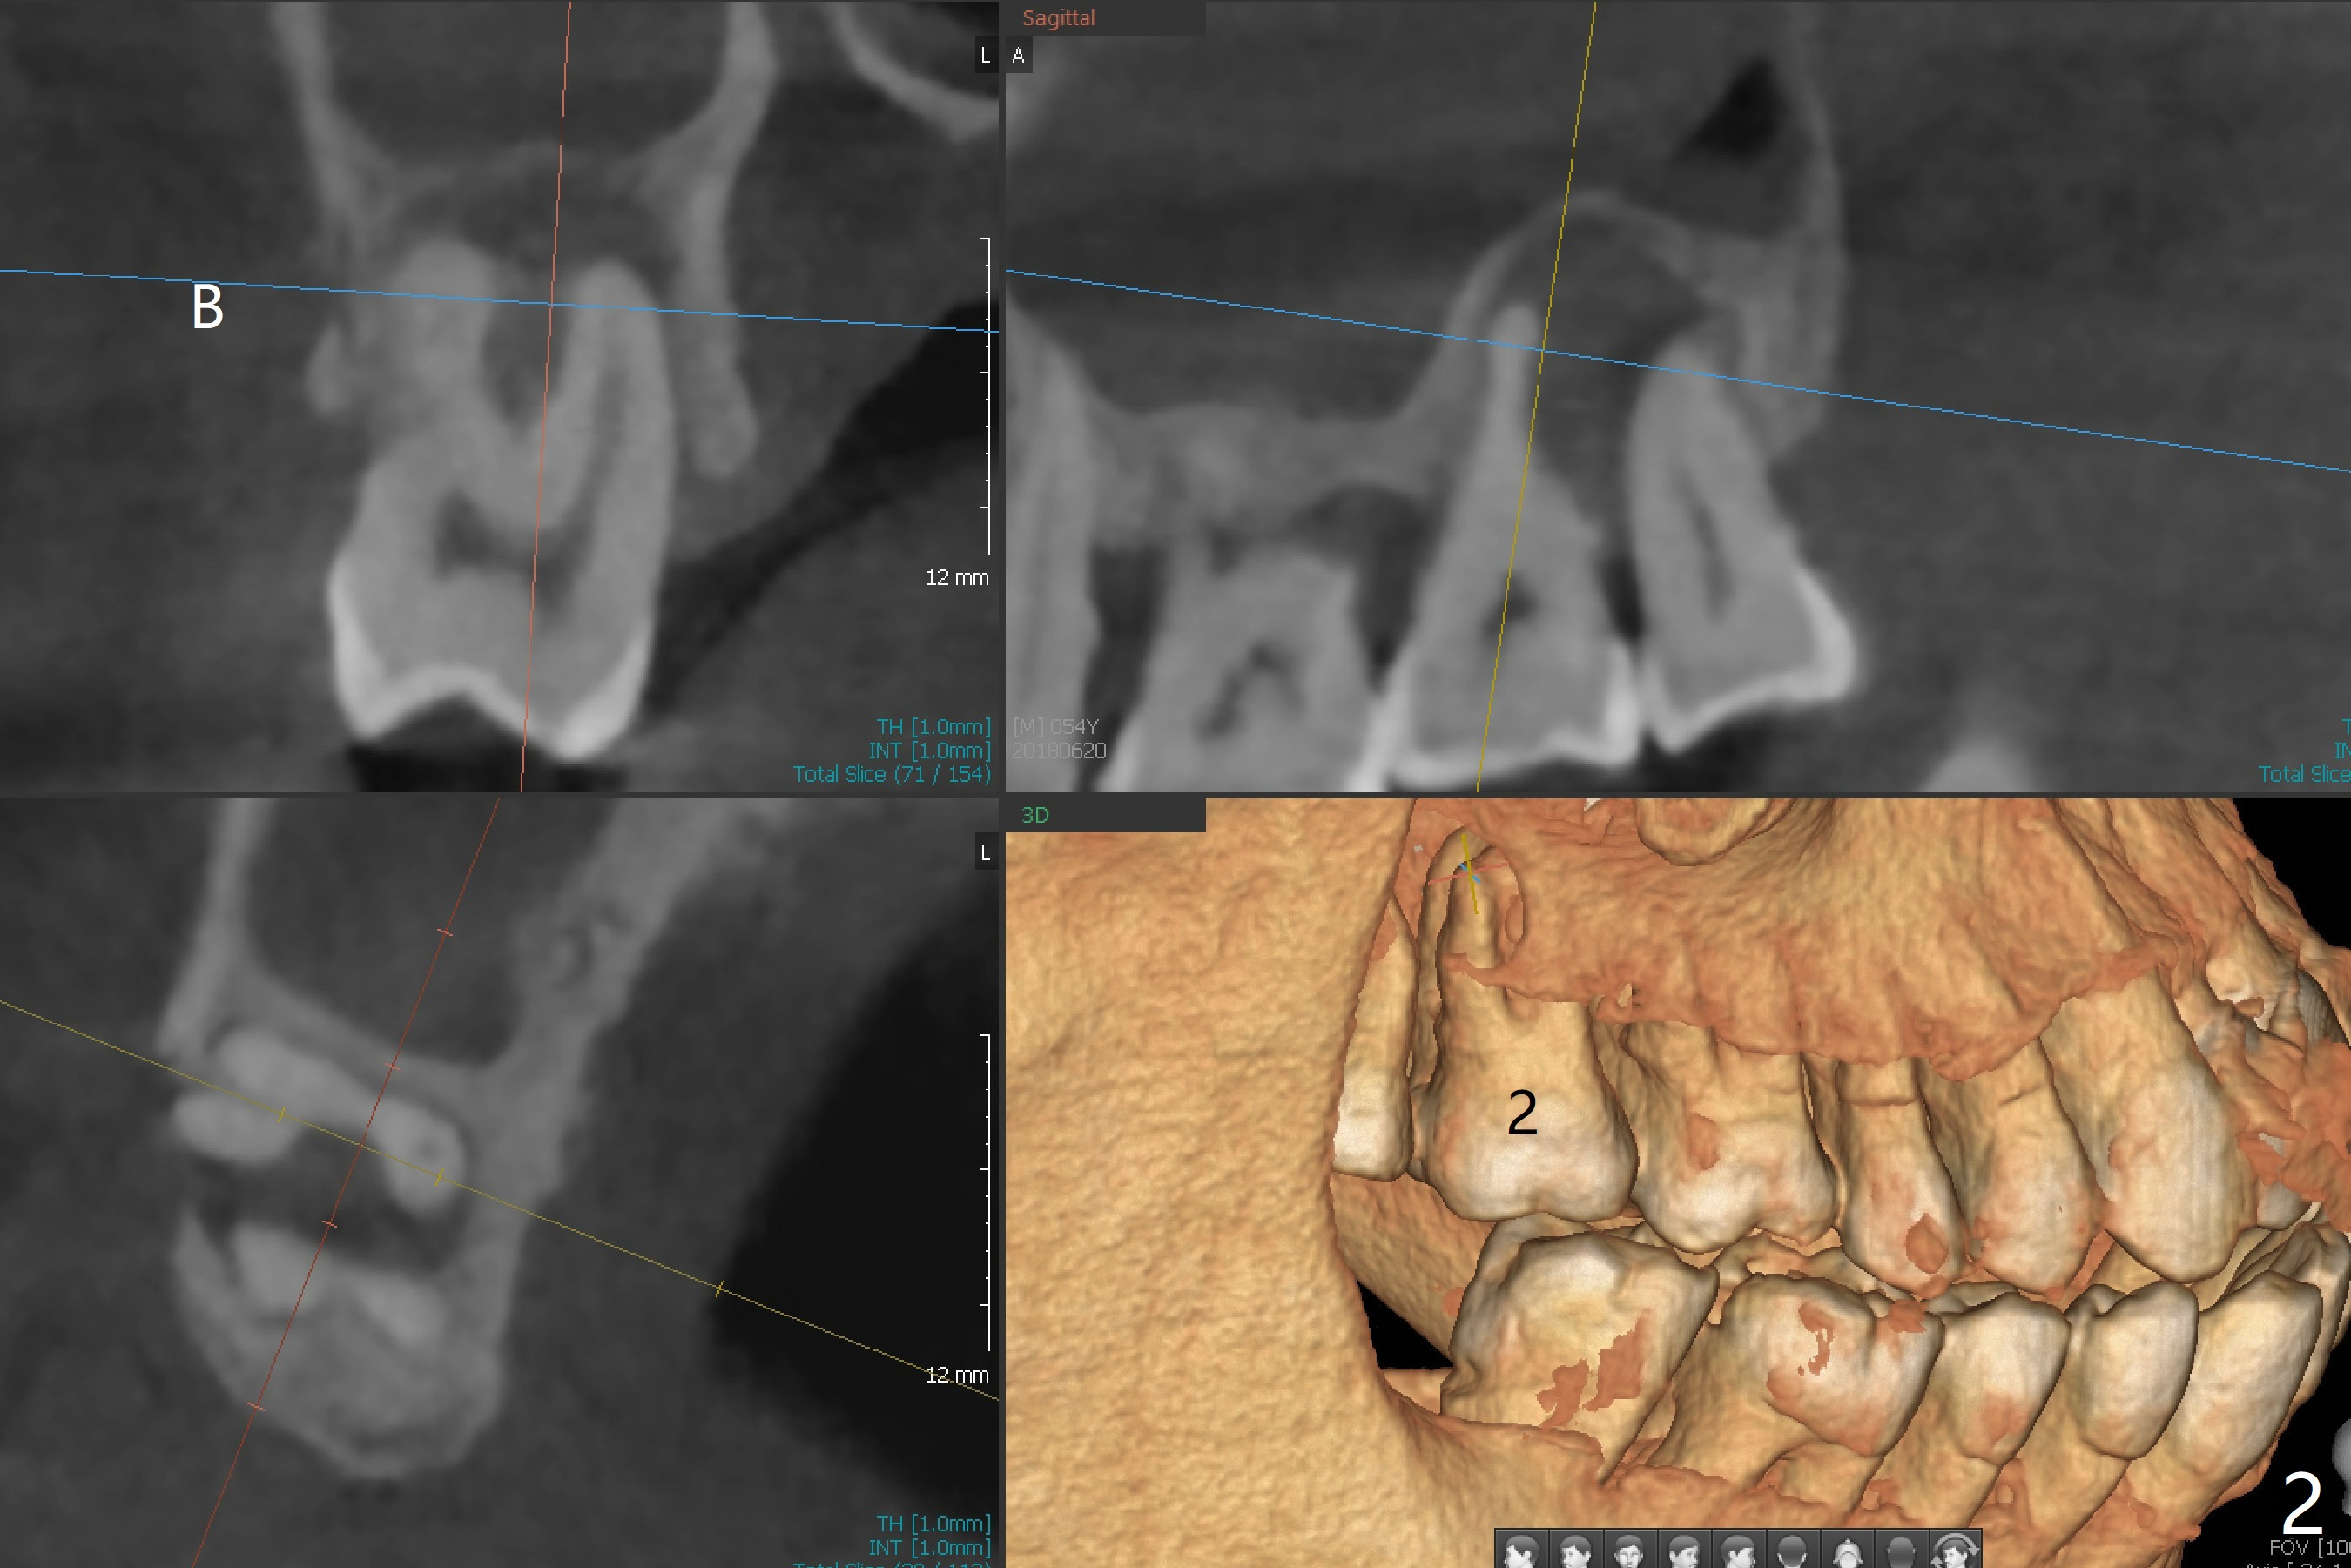

A 54-year-old man presents to office with a request to get a tooth back in the upper left posterior region (Fig.1 #14, wearing RPD). Upon examination, he feels that the tooth #2 is mobile, requiring more urgent care (Fig.2). The infection also involves the tooth #1. Extraction of the latter seems to be imminent. At either site, bone height is limited. Sinus lift is expected with PRF. Place an implant that just passes the sinus floor for stability, e.g., 5-6x10 mm at #2 (Fig.3), but not too long into the sinus. At the 2nd stage (Fig.4), use Magic drill with 2 mm stopper as a tissue punch. Then with 3 mm stopper start osteotomy, followed by Magic lifter, PRF/bone graft and dummy implant or tap. More bone graft and definitive implant. In fact the patient wants to have #14 implant first.